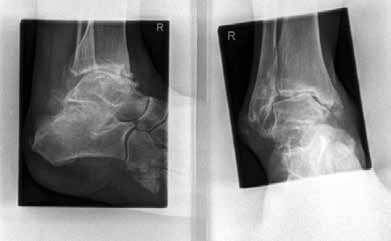

Das besondere Merkmal der Arthrose des OSG ist das relativ junge Alter der Patienten im Vergleich zur Arthrose anderer Gelenke der unteren Extremität, da die meistens zugrunde liegenden Traumata Sportunfälle sind. Zusätzlich werden ein schnellerer Funktionsverlust des Gelenks und eine beschleunigte Progression der Erkrankung bis zum Erreichen des Endstadiums (innerhalb von 10 bis 20 Jahren) beobachtet 9 (Abb. 2a). Negativ beeinflussende Faktoren für die Entwicklung einer Arthrose des OSG sind: Achsfehlstellungen oder angeborene Deformitäten der unteren Extremität, Muskeldysbalance 10, angeborene oder erworbene ligamentäre Fehlentwicklungen, Alter, Geschlecht und genetische Prädisposition 11.

Weiterhin führen Fehlstellungen im Rückfuß zu statischen und dynamischen Überlastungen, da sich bei Varusfehlstellung (Abb. 2a) das Zentrum der Kraftübertragung nach medial und bei Valgusfehlstellungen nach lateral verlagert 47. Die Achillessehne wirkt durch ihren Zug zusätzlich invertierend bei Varusfehlstellung und evertierend bei Valgusfehlstellung auf den Rückfuß ein 48. Möglichkeiten der operativen Therapie sind entweder die einfache Umstellungsosteotomie der distalen Tibia und Fibula als rein supramalleoläre Osteotomie mit dem Ziel einer Überkorrektur des distalen Tibiagelenkflächenwinkels von 3 bis 5° 49 oder die kombinierte Osteotomie an Bein und Rückfuß (Abb. 2b) mit oder ohne Weichteileingriff je nach Topographie der Achsfehlstellung 50. Weitere Möglichkeiten sind die Calcaneusosteotomie, meist als ergänzende Osteotomie nach Wiederherstellung der korrekten Achse (Abb. 2b) im Sinne einer Verschiebeosteotomie, um die Zugrichtung der Achillessehne zu zentrieren, und die Osteotomie der medialen Säule, die bei durch Valgusfehlstellung induzierter Abflachung des medialen Längsgewölbes indiziert sind. Hierbei werden zusätzlich korrigierende Arthrodesen des I. Strahls (Naviculo-cuneiforme-Gelenk, Tarsometatarsalgelenk) oder plantarflektierende Osteotomien (Cuneiforme I oder Metatarsale I) durchgeführt 51.